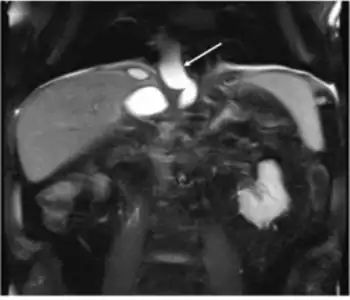

Pseudocyst extends through the hiatus opening to mediastinum